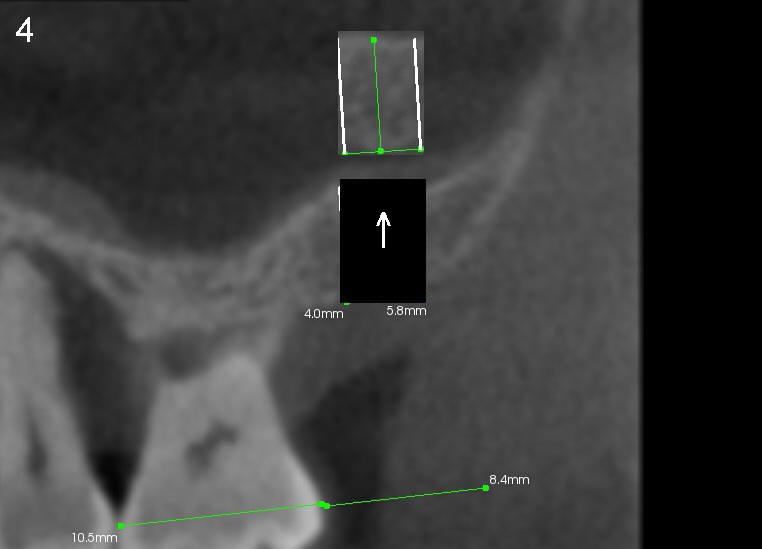

A trephine bur with outside diameter 4 mm will be used to create osteotomy and harvest the bone core (Fig.3; white lines). If the bone does not come out with the trephine bur, it will be pushed upward slowly and gently with a flat end osteotome or tap (Fig.4). When an implant is placed (Fig.5 red outline; 6x11 mm), it is covered by the vital bone above with blood supply coming from the sinus membrane.